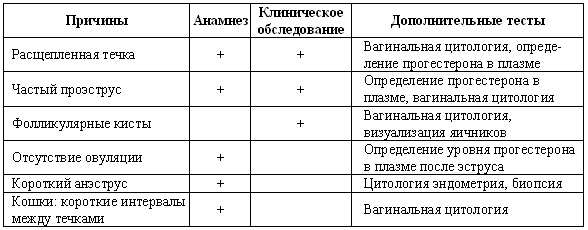

После составления анамнеза можно будет сформулировать текущую проблему как:

• отсутствие проявлений эструса;

• бесплодие, сопровождающееся отклонениями в цикле (короткий интервал интер-проэструса, короткий проэструс, затяжной проэструс/эструс);

• бесплодие на фоне, очевидно, нормального эстрального цикла;

• неспособность к вязке или самопроизвольное прерывание беременности.